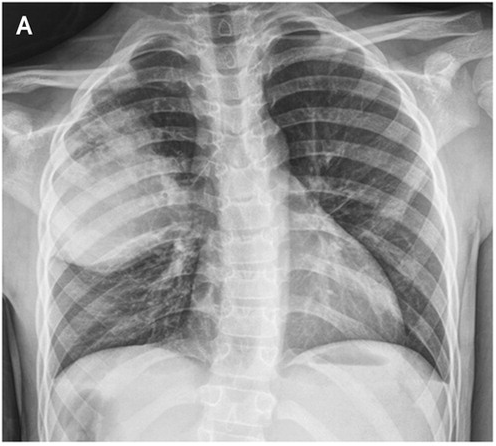

¼Ò¾Æ ³²È¯

fever¿Í chest painÀ¸·Î ÀÀ±Þ½Ç ³»¿ø.

Áø´Ü¸í°ú Ä¡·á ´äº¯ÁÖ¼¼¿ä.